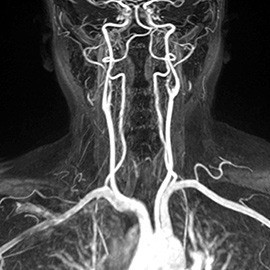

Magnetic resonance angiography (MRA)

Aneurysm

Stenosis

brain tumor

- Certain organs’ blood supply

- Blood vessels